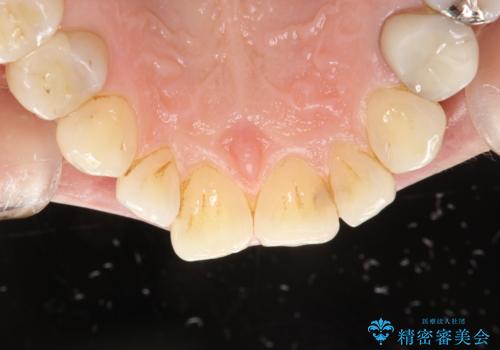

PMTCで歯と歯の間の細かいステインの除去

- 歯磨きでは取れない歯と歯の間の汚れが気になるとのことで来院されました。PMTC60分コースを行いました。

PMTCは、歯に付着した汚れを除去していくため、着色が気になる場合にも行うことができます。ご自身でのセルフケアだけで着色を落とそうとすると、逆に歯を傷つけてしまったり、精密に汚れを除去できないこともあります。また、日常生活で着色しやすい飲食物を避けたりすることはストレスに感じてしまったり、あまり現実的ではありません。

毎日丁寧に歯磨きをしていても、日常生活での飲食物などにより着色してしまうことはあります。PMTCでは、歯の表面の凸凹にミネラルを補給して、ツルツルの表面に仕上げます